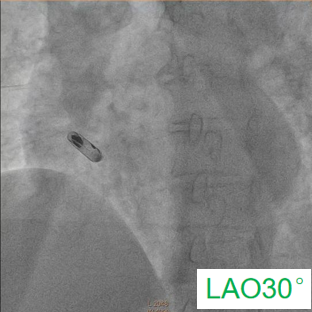

术中,医疗团队经穿刺右侧股静脉建立静脉通路,随后使用猪尾导管分别在RAO30°& LAO30°进行右心耳造影,清晰获取右心耳结构及目标植入位置,最终成功于右心耳基底部植入心房无导线起搏器,手术全程顺利。术后患者各项参数稳定,恢复良好,次日便出院,真正实现了“介入操作、快速康复”。